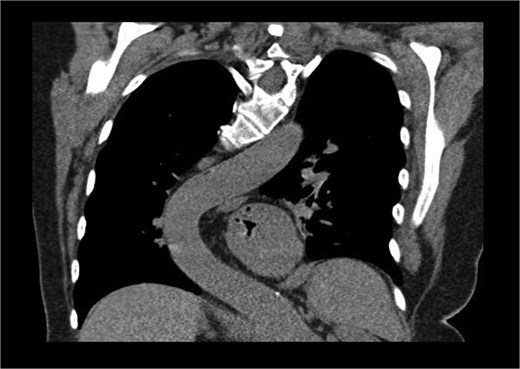

The patient’s comorbidities were extensive and included: heart failure with preserved ejection fraction (HFpEF), atrial fibrillation, left atrial enlargement, Barrett’s esophagus, hypertension, hypercholesterolemia, multiple benign hepatic cysts, osteoporosis, a large sliding hiatal hernia containing the gastric fundus and celiac artery, and descending thoracic aortic tortuosity causing chronic left lower lobe segmental atelectasis (Fig. 2).

Coronal CT showing curvature of the thoracic aorta tortuosity compressing the distal esophagus and causing chronic left lower lobe segmental atelectasis.